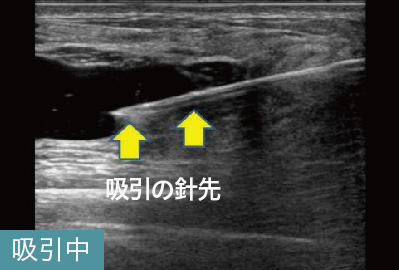

ただし、ヒアルロン酸注入による豊胸後にしこりを発見しても、ヒ アルロン酸が原因かどうかをまずはきちんと検査することが欠かせません。さらにヒアルロン酸を完全に取り除くため、溶解注射を打つ際にも超音波エコーなどの映像を確認しながら、的確に注入することが大切です。

このケースは、他院でヒアルロン酸溶解注射による治療を受けても残ってしまったしこりの治療でした。しこりの取り残しは、治療前にしこりの正確な位置を把握していなかった可能性が考えられます。当院では、実際にしこりを確認しながらヒアルロン酸内に的確に注射を行います。このケースでも完全になくなっていることが確認できます。